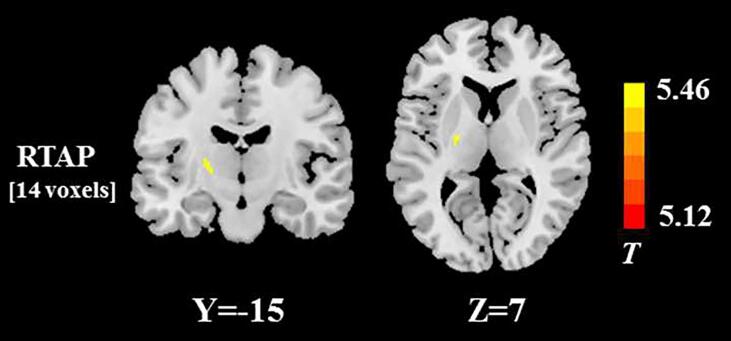

In the subgroup analysis using the VBA, the significant RTAP reduction was found in left posterior limb of internal capsule in the ALS patients with both bulbar and limb involvement, compared with those with limb-only involvement (Fig. 5). No significant differences in the other DTI, DKI, NODDI, and MAP metrics were found between the two ALS subgroups, after family-wise error correction for multiple comparisons.

Fig. 5.

White matter regions with the significant RTAP difference between two ALS subgroups stratified according to the presence or absence of bulbar involvement. The spatial extent of WM area is indicated by total voxel number. Left and right sides of the image respectively indicate the left and right hemisphere of brain.

In consistence with previous report that the extent of WM impairment is associated with clinical involvement in ALS (Broad et al., 2019), we found the more widespread RTAP reduction in the subgroup with both limb and bulbar involvement compared to those with limb involvement alone. Thus, our findings also suggested the potential of MAP measurements for assessing the effect of ALS disease heterogeneity on WM microstructures. On the other hand, no significant difference related to bulbar impairment was observed in other diffusion parameters (e.g. NODDI metrics), which didn’t keep in line with previous studies (Broad et al., 2019). This discrepancy may be due to the differences in the sample collection and MRI data acquisition and processing between the current and previous diffusion studies.